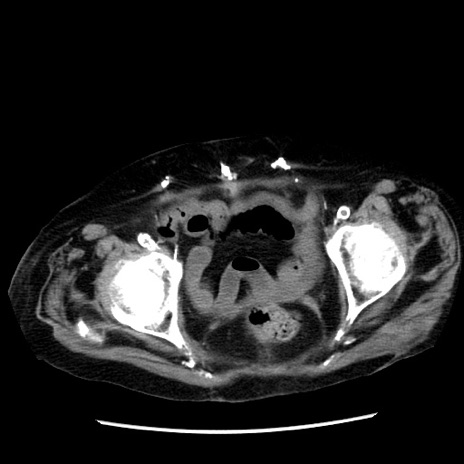

冠状断像

【症例】 90歳代女性

【主訴】 腹痛・嘔吐

【現病歴】今朝から左側腹部痛を認めた。 経過観察していたが、嘔吐を認めたため来院。

【既往歴】 子宮癌術後

【身体所見】 意識清明、BP 127/54mmHg、P 98bpm Sp02 95%(RA)、BT 35.8°C、腹部平坦・軟腸ぜん動音聴取良好、右下腹部圧痛(+) 反跳痛なし

【データ】WBC 9800、CRP 0.46